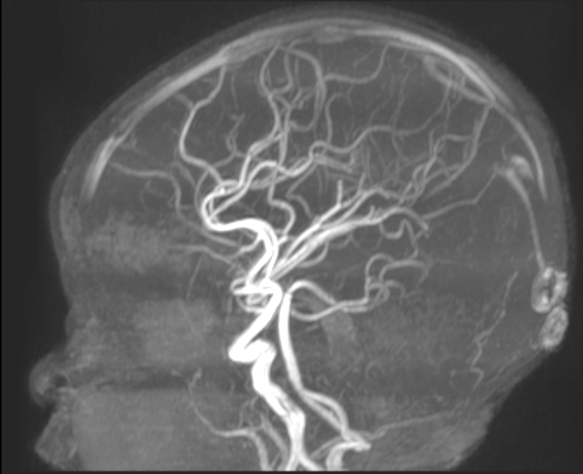

An MRI revealed that Maryam had hemimegalencephaly, a rare neurological condition where one half of the brain is enlarged and can cause epilepsy, developmental delays and muscle weakness. In this case, it had affected the left hemisphere of Maryam’s brain. She was immediately rushed to The Hospital for Sick Children (SickKids).

And at every step, the Interventional Neuroradiology team, Epilepsy and Neurosurgery teams worked together, using detailed electroencephalogram (EEG) and brain MRI scans to ensure precision and safety.

Now, months later, Maryam has not had a single seizure since July 2024.

“She went from having seizures about every two minutes to having one or two per day, to then having zero, which is incredible,” says Muthusami.